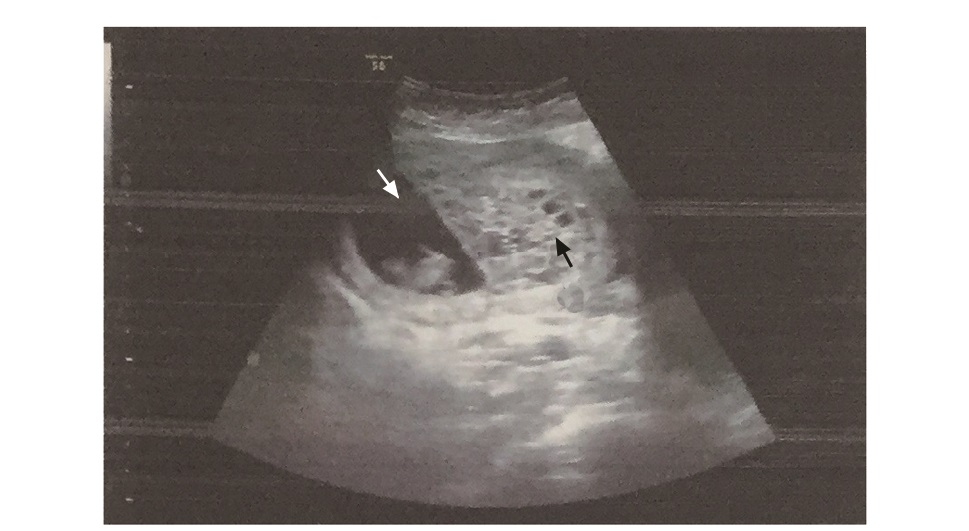

Abstract: Hydatidiform mole is a benign gestational trophoblastic disease. Twin pregnancy with hydatidi-form mole and a coexistent fetus is extremely rare. The diagnosis is usually delayed and the pregnancy is often terminated due to severe vaginal bleeding or other complications. There are few guidelines for termination methods. Here we report a case of successful labor induction and vaginal delivery of twin pregnancy with hydatidiform mole and a coexistent fetus at 16 weeks of gestation. The diagnosis, treatment principles, and termination methods are discussed.